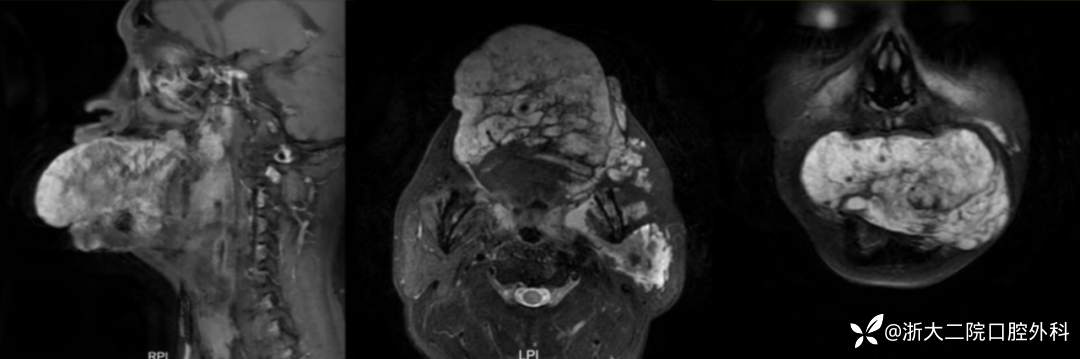

那么是否会是囊肿或其他血管畸形?治疗团队随即安排患者进行了舌部的增强磁共振检查,结果提示病灶为静脉畸形,且遍布患者左侧的舌-咽旁、颌面间隙、颌面部软组织及左侧腮腺。

img

患者 MRI 结果